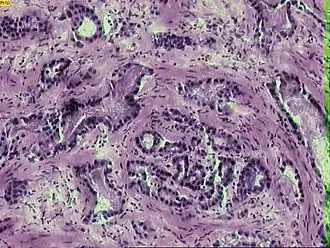

Микрофотография инвазивной аденокарциномы простаты | |

Рак предста́тельной железы́ (рак проста́ты, карцино́ма проста́ты, карцино́ма предста́тельной железы́; англ. prostatic cancer, лат. adenocarcinoma prostatica) — злокачественное новообразование, возникающее из эпителия альвеолярно-клеточных элементов предстательной железы.

Гистологическая классификация

К В. Л. Бялику (1971) восходит следующая гистологическая классификация рака предстательной железы, по которой он подразделяется на следующие формы[11]:

- 1) недифференцированные:

- полиморфноклеточный рак (характеризуется большим количеством делящихся различных по форме и размерам клеток);

- 2) малодифференцированные:

- анапластическая аденокарцинома (характеризуется изменением внутриклеточных структур, специфическими формой и размерами клеток);

- солидный рак (при котором клетки располагаются пластами или тяжами, разделёнными прослойками соединительной ткани);

- скиррозный рак (при котором опухоль становится твёрдой, фиброзной за счёт преобладания соединительнотканной стромы над опухолевыми клетками);

- 3) дифференцированные:

- аденокарцинома (если рак возник из железистого эпителия);

- плоскоклеточный рак (если рак возник из плоского эпителия);

- тубулярный рак (если рак развился из узких каналов, выстланных кубическим или призматическим эпителием, в просвете которых может находиться секрет);

- альвеолярный (возникает из концевых отделов ветвящихся желез).

Около 95 % случаев рака предстательной железы составляют ацинарные аденокарциномы; на долю же остальных видов аденокарцином (протоковая, муцинозная, мелкоклеточная, переходно-клеточная) приходится не более 5 %[12]